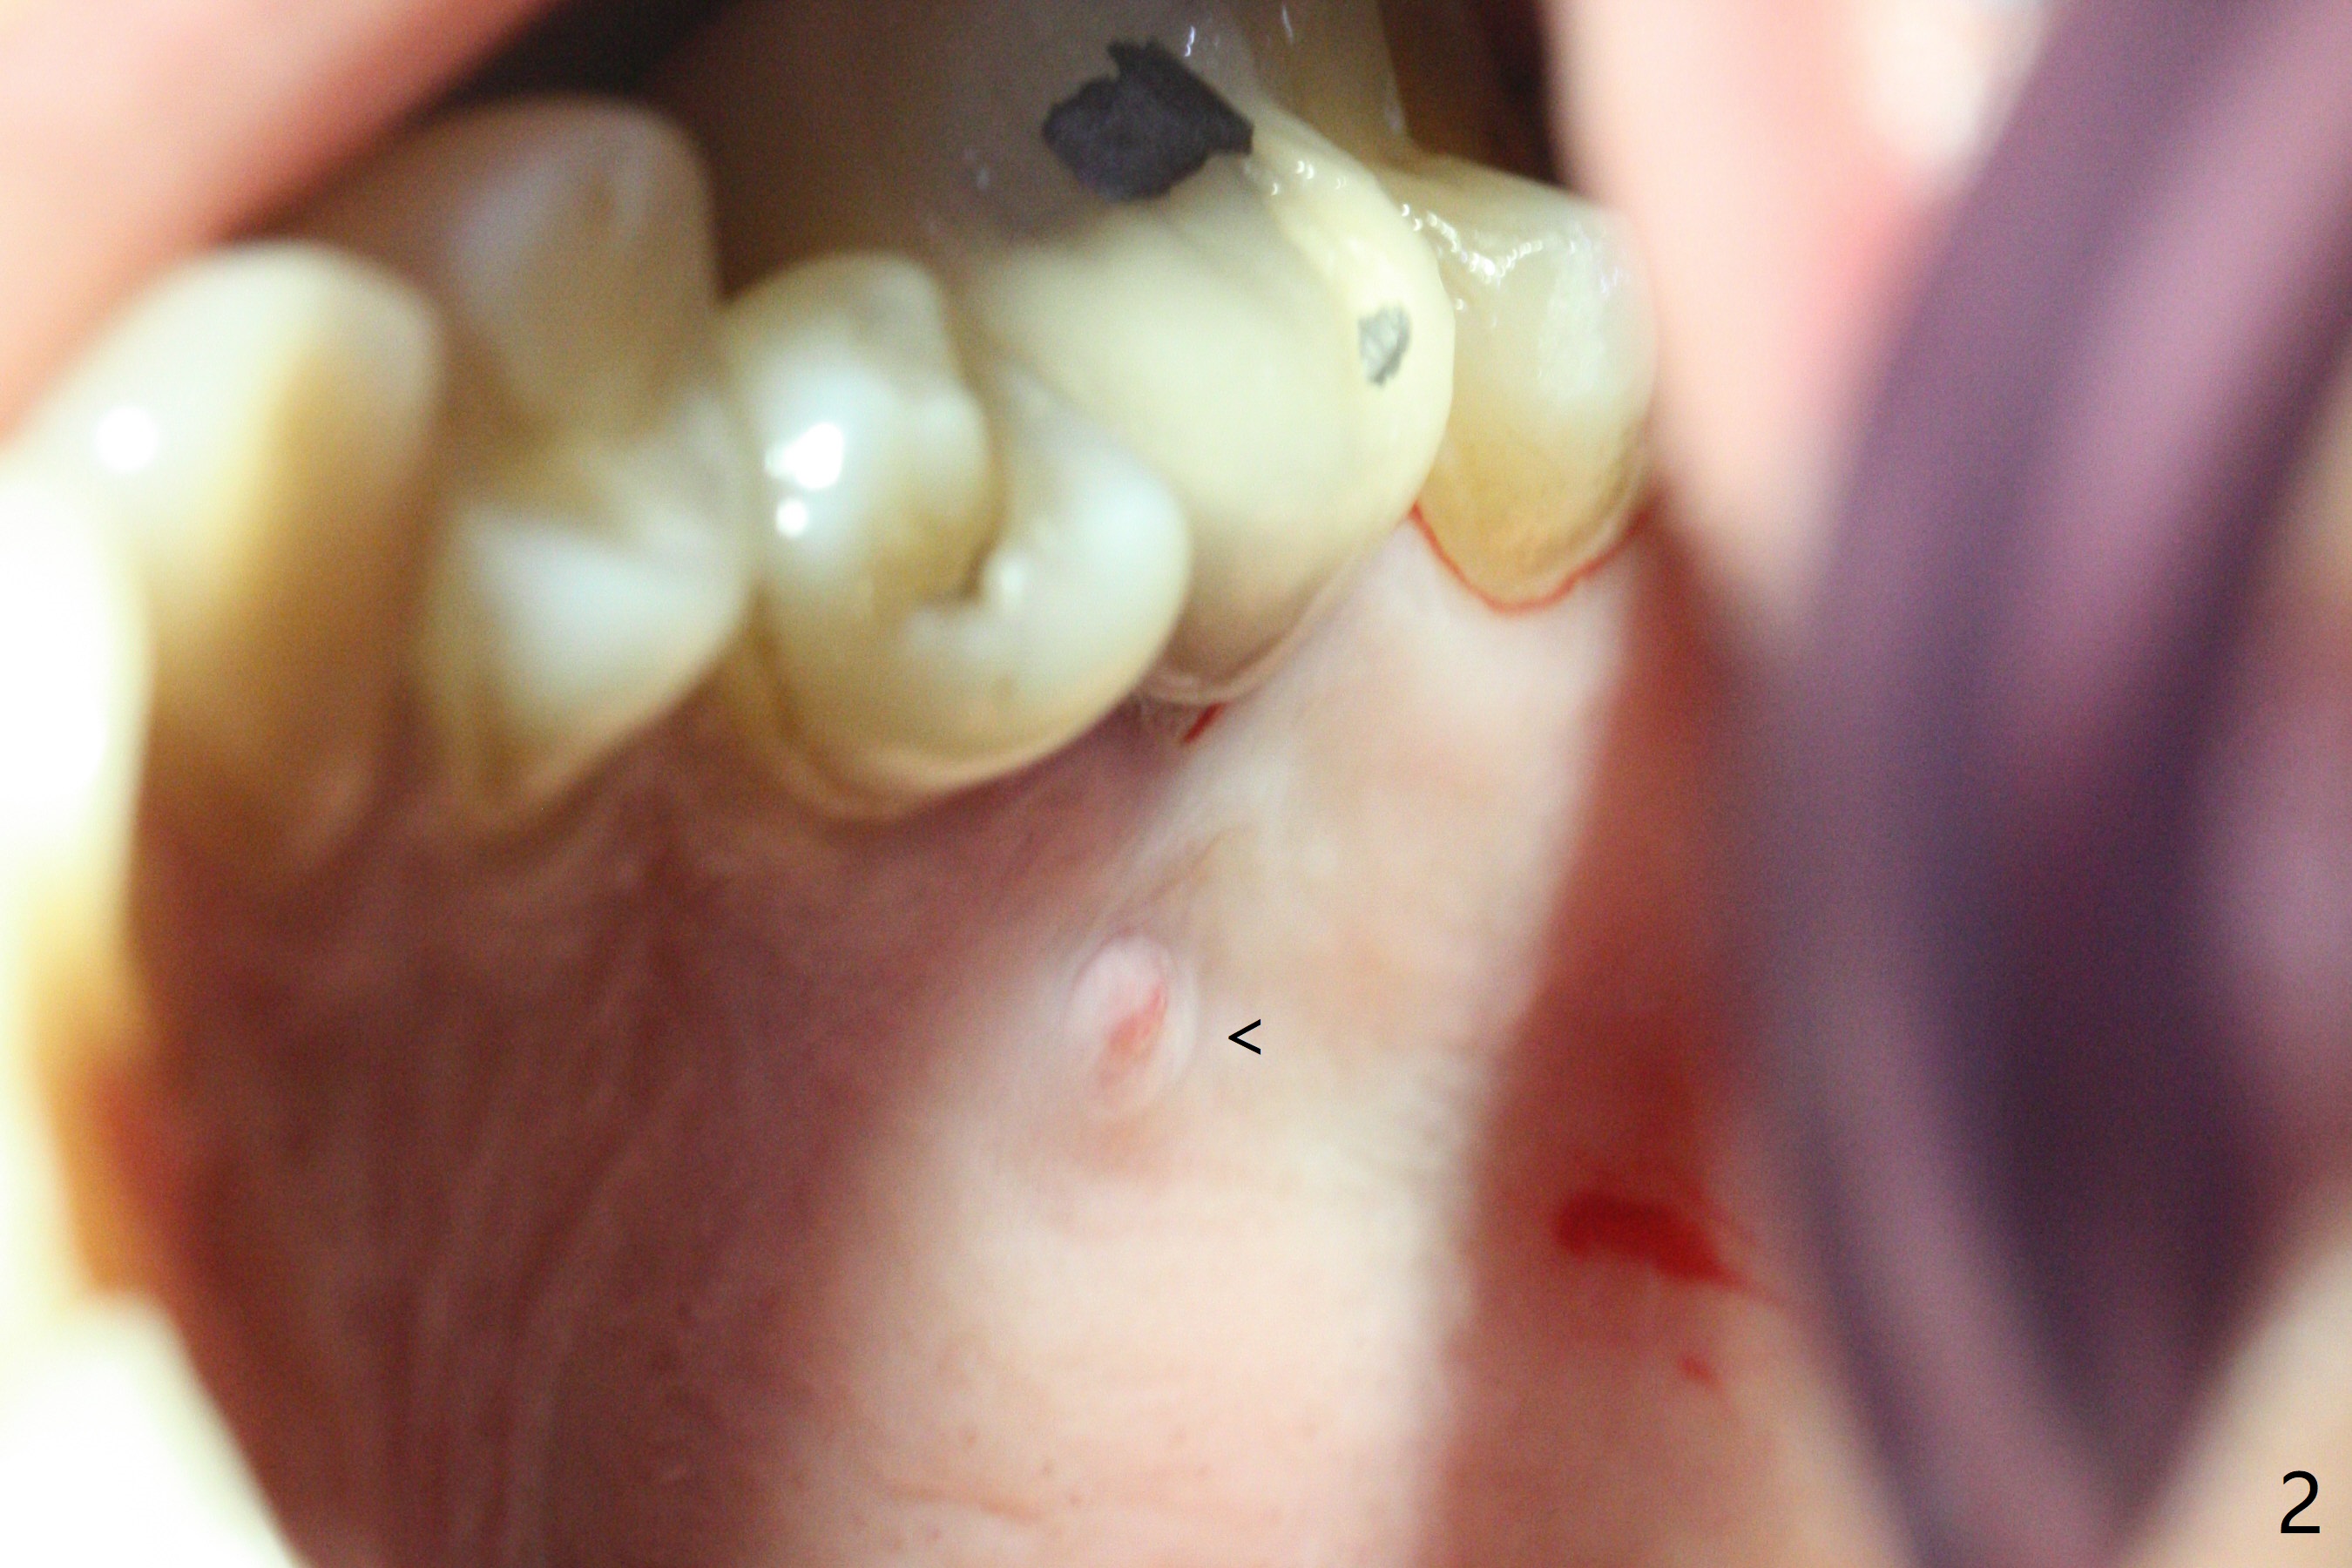

A 29-year-old man has pain in the upper left quadrant. It appears that the tooth #14 has endo and post failure with palatal fistula (Fig.1,2). The septum is almost non-existent; the palatal wall is low, while the sinus floor is present. Sticky bone is placed first against the defective palatal wall and presumably pushed as high as to the sinus floor (Fig.3-5). PRF plug/membrane and 6-month membrane are used to close the socket with 4-0 Chromic gut suture apparently securely, followed by periodontal dressing. Examination of the extracted tooth shows granulation tissue between the roots (Fig.6 *). Underneath the granulation tissue is cement-like material (Fig.7 C). Distal-to-mesial X-ray examination shows possible furcation perforation (Fig.8 *), while mesial-to-distal one the cement-like material in the furca and pulpal chamber as well as MB2 (Fig.9 >). The patient returns 8 days postop, reporting pain reduction, but wants to have #16 extracted. The periodontal dressing is loose, but stuck with 2 sutures underneath. When the dressing is removed, the wound looks normal (Fig.10). In fact the dressing is re-applied. The 6-month membrane has lost 1 month postop. The majority of the socket heals except the palatal (Fig.11 *), as related to the existing palatal fistula/defect (^). Orthodontics is being considered. If the buccal plate collapses 4.5 months post extraction, socket shield should have been done. In fact the buccal plate is robotic, while the bone density is low palatal in CT (Fig.12).